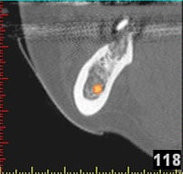

(siehe Bild 3 und 4).

Mit diesen gewonnenen Informationen und Planungen stellt der Zahnarzt interaktiv spezielle Bohrschablonen her. Diese ermöglichen eine exakte Positionierung der Implantate, so wie vorher am Computer geplant.

Weiterhin ist eine auf diese Weise geplante Operation für den Patienten weit weniger belastend. Denn die Freilegung des Knochens ist auf ein Minimum reduziert.